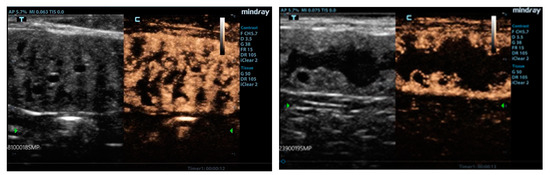

3.1. Ultrasonographic Examinations